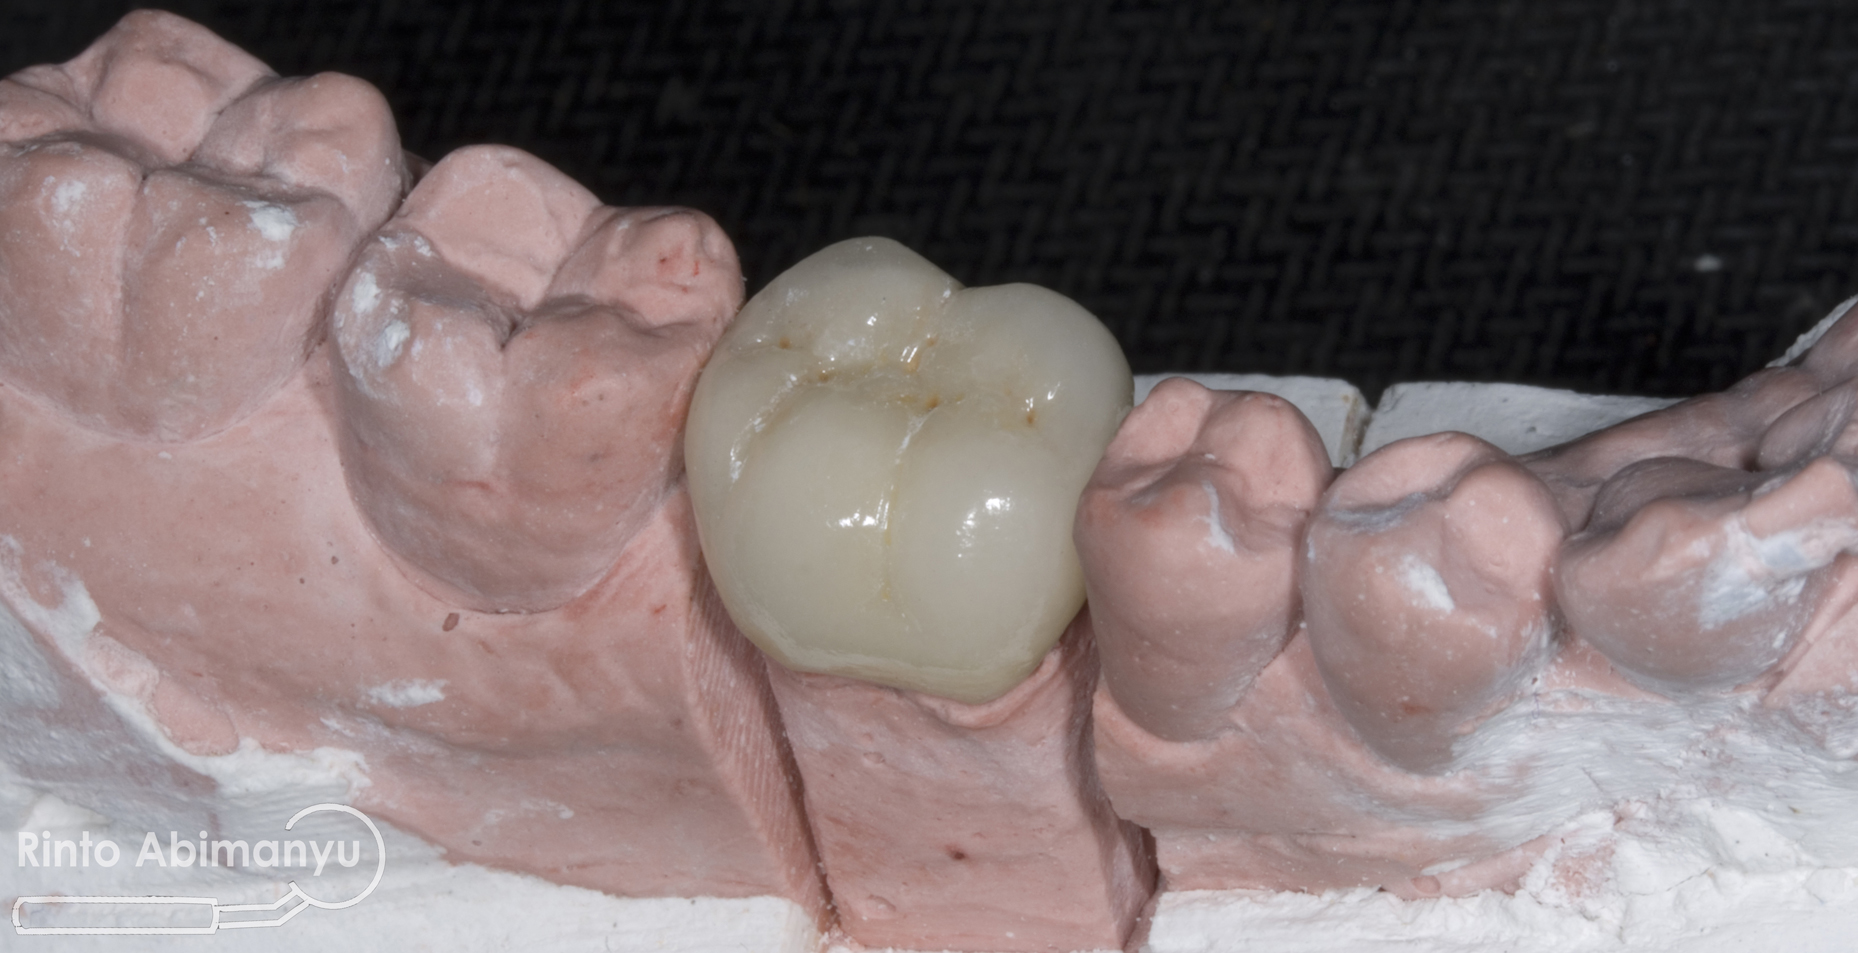

Crown yang saya buat adalah Porcelain Fused to Metal (PFM) dan begini tampilannya sesaat setelah dikirim dari lab…